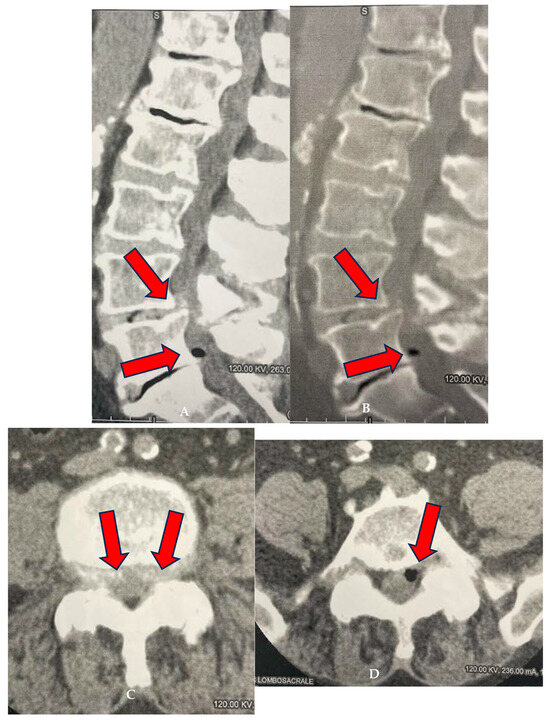

The procedure involved injecting 3 cc of the O2-O3 gas mixture at a concentration of 25 μg/mL, followed by retracting the needle a few millimeters to inject another 5 cc of the mixture to treat the region surrounding the facet joint (Figure 5). This technique is well established and widely documented in the international literature, e.g., [20,21,22,23]. For patients suffering from facet syndrome, the infiltration was performed both at the level of the facet joints and the intervertebral foramina, while for patients with disc-related pathology, the treatment was limited to intraforaminal–periganglionic injections, in line with guidelines reported in literature, e.g., [20,21,22,23,26,30,33].

Figure 5.

Low-dose CT scan for proper distribution of the gas mixture after infiltration (arrows).

After the injection, a further CT check of the correct distribution of the gas mixture was performed (Figure 5).